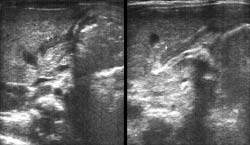

УЗИ позволяет видеть пилорическую оливу в продольном и поперечном срезах, определять характер перистальтики желудка и наблюдать продвижение желудочного содержимого через пилорический канал. При гипертрофическом пилоростенозе натощак в желудке обнаруживают большое количество жидкого содержимого, перистальтика глубокая, «перетягивающая». Пилорический канал при прохождении перистальтической волны не раскрывается. Длина канала составляет в среднем 21 мм (от 18 до 25 мм), наружный диаметр привратника 14 мм (от 11 до 16 мм). Циркулярная мышца представлена на продольном разрезе двумя параллельными гипоэкогенными полосками, между которыми располагается эхогенная полоска слизистой оболочки. На поперечном срезе циркулярная мышца визуализируется в виде гипоэхогенного кольца вокруг эхогенного кружка слизистой оболочки. Толщина мышцы составляет в среднем 5 мм (от 3 до 6 мм) (Рис. 4).

[Увеличить]

Рис. 4. Больной В., 1 мес. Врожденный пилоростеноз.